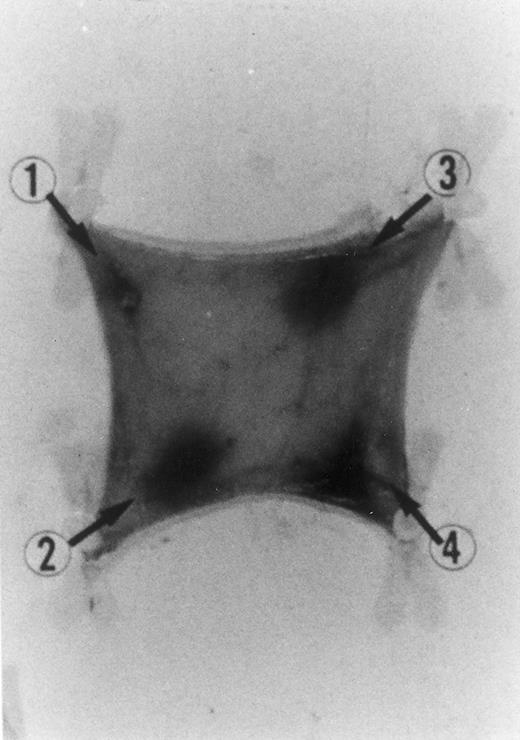

Chemotactic effect of human recombinant RANTES and MCP-1 on basophilic cells.Recently it has been reported that RANTES and MCP-1, -2, and -3 are chemotactic agents for human T lymphocytes.23 26 In this study we evaluated the selective chemotactic effects of RANTES and MCP-1 on basophilic cells. Figure 3 shows an increased number of basophilic cells after a 50 μL intradermal injection of FMLP (10−6 mol/L), RANTES 10 ng and MCP-1 10 ng, while PBS (vehicle) did not produce any appreciable effect. The infiltrated basophilic cells were colored with Toluidine blue (0.1%) and counted in the optic field using a grating of size 5 × 5 mm, under an optic microscope (× 40). In Table 2 results indicate that RANTES at 20 and 10 ng is more potent than equal doses of MCP-1 (<0.05 and 0.01, respectively). The highest number of basophilic cell accumulation in the skin injection sites was obtained with LPS (10 ng/50 μL) (193 ± 21), while FMLP (10−6 mol/L) (127 ± 14) was found to be less effective.

Basophilic cell migration induced by human recombinant RANTES 10 ng (C) and MCP-1 10 ng (D) into sites of injection. The sections were stained with Toluidine blue (0.1%) and analyzed at a magnification of ×40 (Nikon Diaphore). (A) represents a control and (B) is a positive control where FMLP was used at 10−6 mol/L. This representative experiment was found to be reproducible and has been performed at least three times.